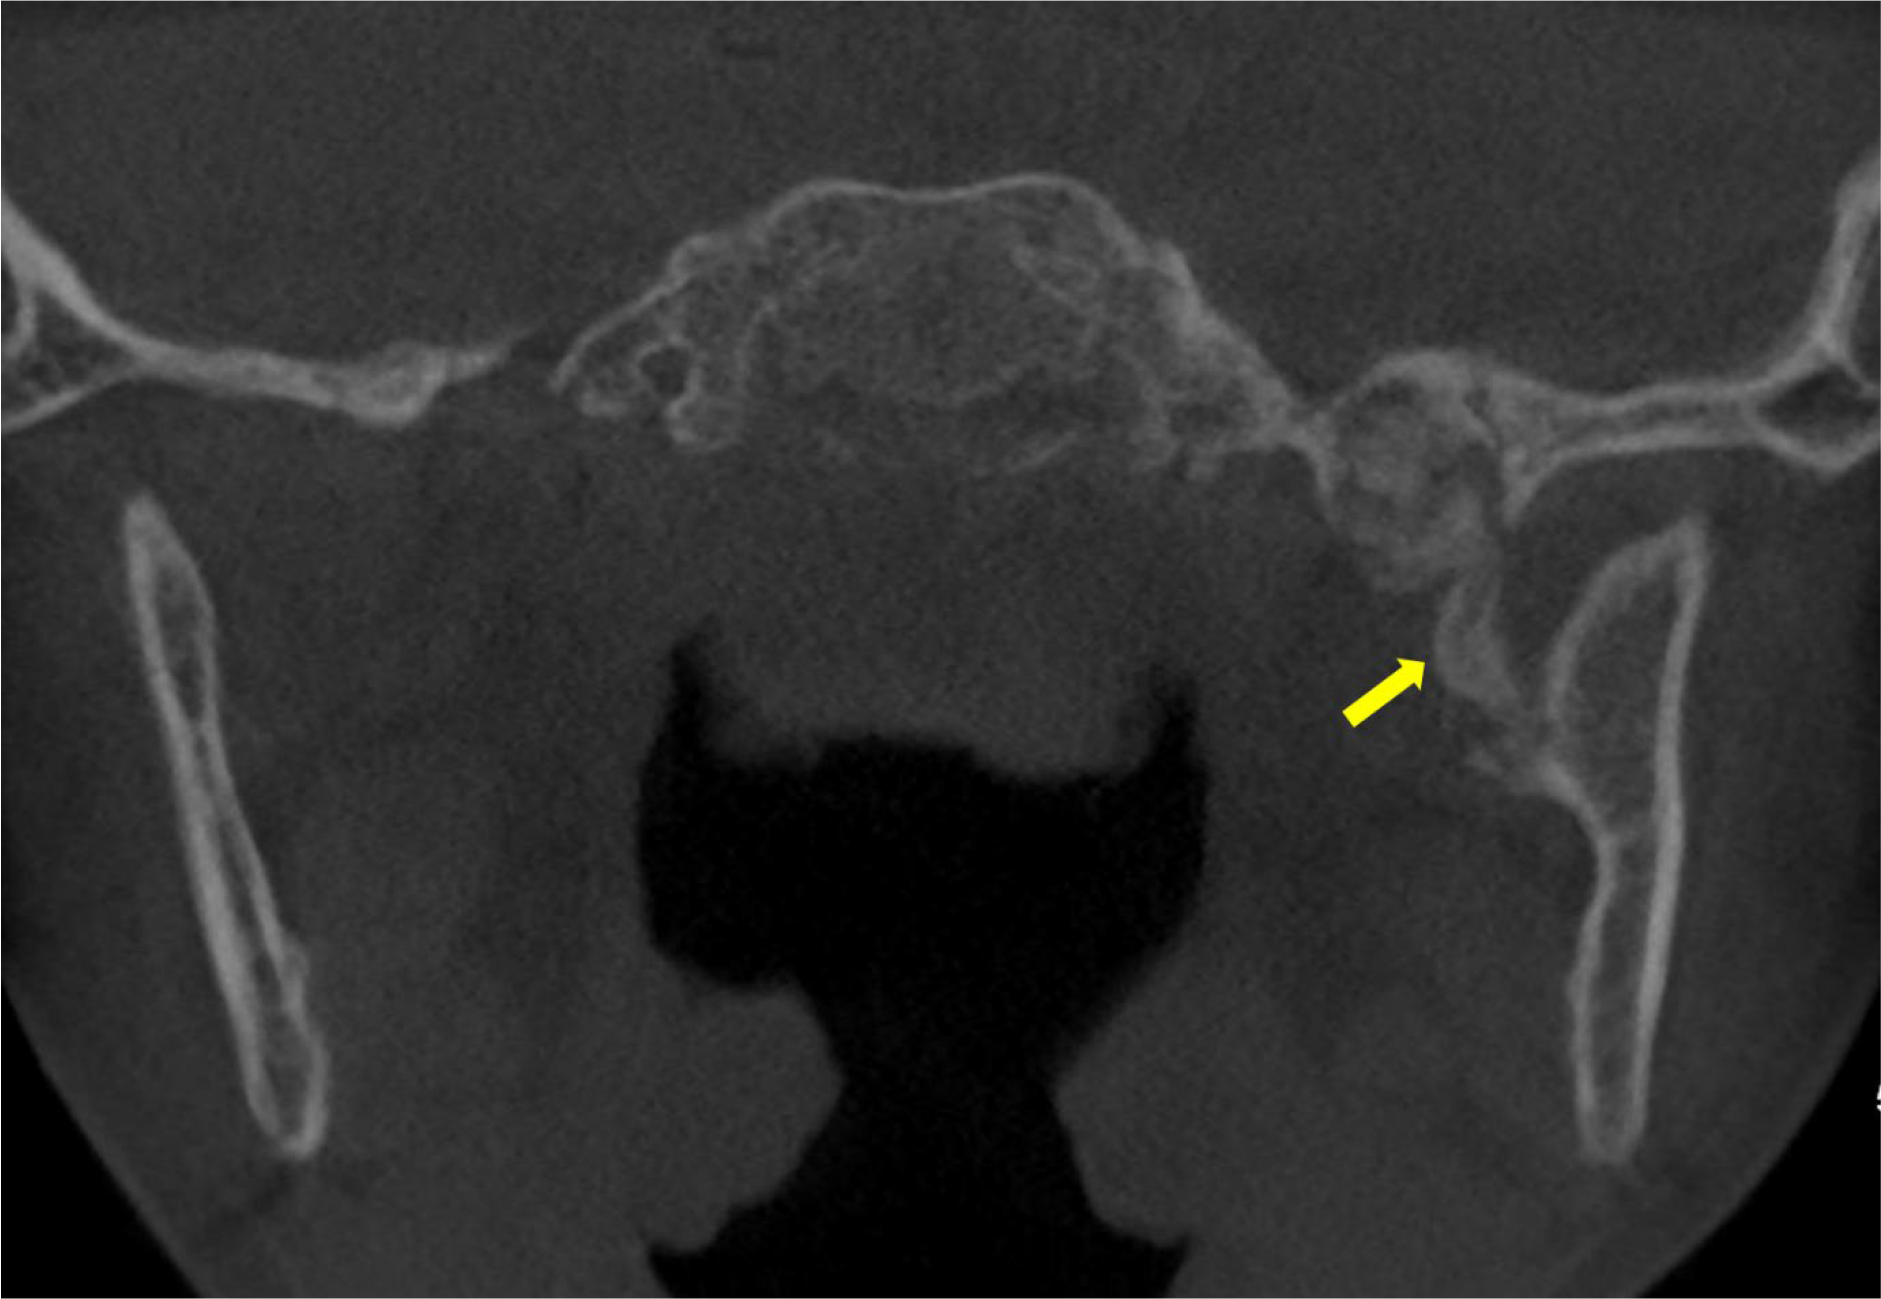

Figure 1

Unenhanced CT scan showing an ossified structure located between the left mandibular ramus and the spine the left sphenoid (arrow).